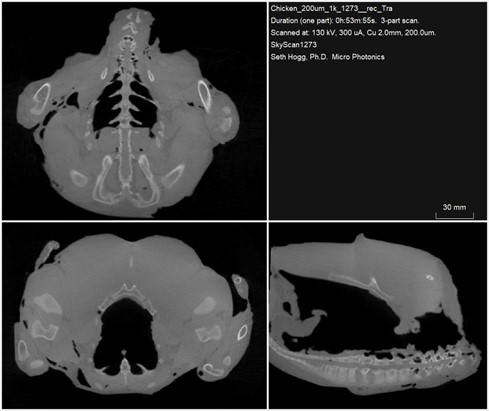

For our article this month, we imaged a grocery store chicken using the SkyScan 1273 desktop micro-CT. As can be seen from the view in Figure 1 above, the large sample volume of the SkyScan 1273 allowed us to image the whole sample intact. With the versatility of the SkyScan 1273, we first imaged the entire chicken at a voxel size of 200um as a quick, overview scan of the sample. We then went back and imaged just the chicken neck, which was removed during processing of the chicken, using a higher resolution with a 25um voxel size. All our SkyScan instruments allow for lower resolution imaging to be done quickly for general overview imaging by binning the pixel detectors. Each also maintains the ability to complete imaging at high resolutions.

Figure 2: Planar views of reconstructed data from the whole chicken sample

As shown in Figure 2, the SkyScan 1273 was able to quickly provide a general overview of the bone location and condition within the chicken. Without the addition of a contrast agent, all soft tissue appears similar, though some regions of higher fat concentration can be observed based on the differences in X-ray attenuation through fat and through soft tissue. Because fat contains less water and is lower density than soft tissue, these regions appear darker in our final reconstructed images since the fat regions attenuate a lower percentage of X-rays than the soft tissue or bones. The large sample size and high density arising from both bone and several inches of soft tissue required the use of all 39W of power available on the high-energy SkyScan 1273 to produce these clean images.